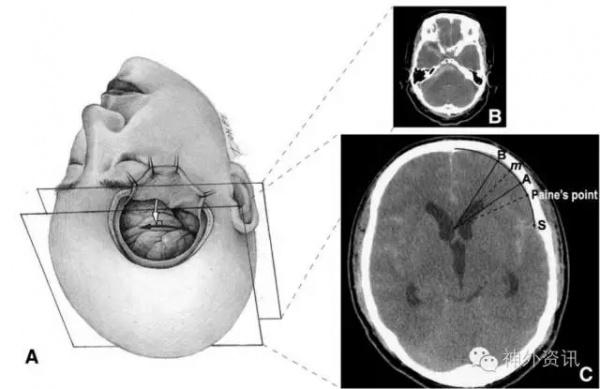

改良Paine’s点穿刺

对于H&H分级、Fisher分级较高的SAH病例,经终板三脑室切开引流置管术是达到Slack brain的方法之一,在有些神经外科中心,经Paine’s点穿刺侧脑室引流置管术应用较多,亦有学者提出了改良Paine’s点的理念。(Revision of Paine’s technique for intraope rative ventricular puncture,Jaechan Park,Surgical Neurology 70(2008)503-508)

一个理想的穿刺道,应该穿越最少的脑组织,避开重要的神经皮质及核团。如图8的m点相比Paine’s点,有效避开了内囊前肢及尾状核头,距离Broca区更远,穿刺道亦明显缩短。

Paine’s点的穿刺方法为垂直眶外侧壁2.5cm,额叶侧垂直侧裂2.5cm,垂直皮质深度约5cm。经大量统计数据测量,改良Paine’s点(见图8、图9)即m点为垂直眶外侧壁2.5cm,额叶侧垂直侧裂4.5cm,深度约4cm。

图8. 改良Paine’s点穿刺。

图9. 改良Paine’s点穿刺。